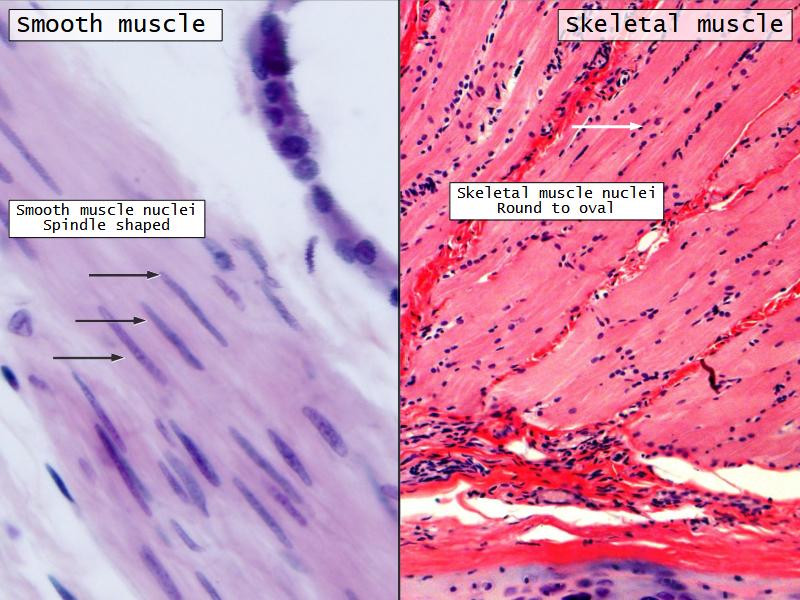

Name three types of contractile cells.

Bronchi - Transitions

- Intrapulmonary bronchi

- Irregular cartilage

- Respiratory epithelium

- Glands

- Bronchioles

- Smooth muscle REPLACE cartilage

- Ciliated columnar > Ciliated cuboidal

- NO glands - goblet cells -> secretory cells

- Terminal bronchioles

- Smooth muscle

- Ciliated cuboidal epithelium